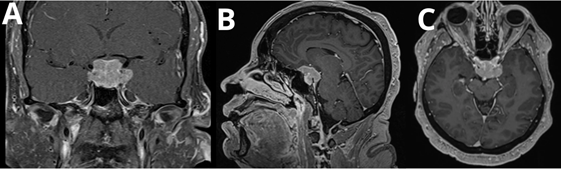

A 57-year-old postmenopausal woman with a medical history of diabetes mellitus, hypertension and dyslipidemia. Her surgical history is remarkable for hysterectomy for uterine fibroids 12 years ago. She presented to our hospital in early 2023 complaining of headache, nausea, vomiting, and blurred vision. Investigations was done and found elevated prolactin level of 2000 ng/mL (5.18-26.53 ng/mL) and MRI findings of a 2.1 cm expansive pituitary fossa with dural extension. Diagnosis of pituitary macroprolactinoma was made, and patient was started on cabergoline (0.5 mg orally once weekly). In addition, her laboratory results also showed panhypopituitarism (central hypothyroidism, secondary adrenal insufficiency, and hypogonadism), for which she was commenced on appropriate hormonal replacement therapy. By December 2023, the patient experienced worsening symptoms, including headaches, nausea, vomiting, and blurred vision in the left eye. Repeated MRI at this time revealed an increase in the pituitary mass size to 3.2 cm with optic chiasm compression (Figure1).

Figure 1 T1 post-contrast images in coronal (A), sagittal (B), and axial (C) views, demonstrating a sellar lesion with diffuse homogeneous enhancement pre-operatively.